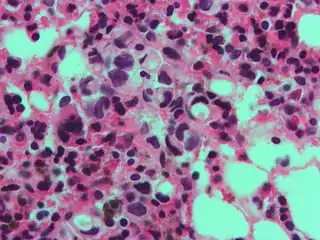

Gastric signet ring cell carcinoma. H&E stain.

The name of the cell comes from its appearance; signet ring cells resemble signet rings. They contain a large amount of mucin, which pushes the nucleus to the cell periphery. The pool of mucin in a signet ring cell mimics the appearance of a finger hole and the nucleus mimics the appearance of the face of the ring in profile.